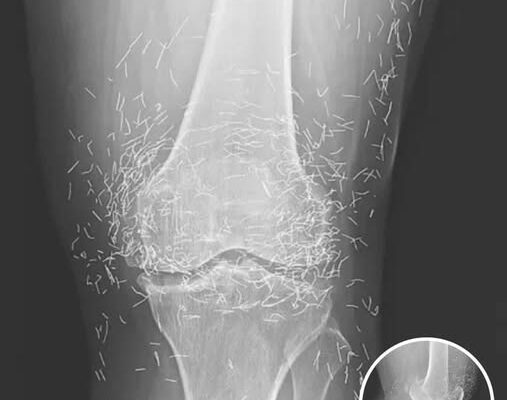

A routine X-ray revealed an unexpected surprise when doctors examined the knees of a 65-year-old woman suffering from severe joint pain. What they found was nothing short of astonishing — hundreds of tiny gold needles embedded deep in her tissue.

A X-ray of the patient’s knee showing acupuncture needles embedded in the tissue, Photo Credit: Reddit

As for the South Korean woman, her case was recently documented in the New England Journal of Medicine. While the needles may have been intended to help, her X-rays tell a cautionary tale about the potential risks of extreme alternative therapies.